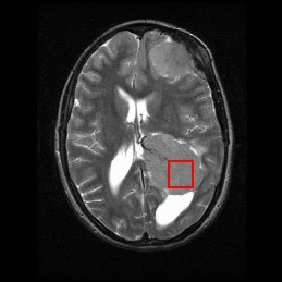

Shown below is an MRI brain scan (in the axial plane, that is slicing from front-to-back and side-to-side through the head) showing a brain tumor (meningioma) at the bottom right. The red box shows the volume of interest from which chemical information was obtained by MRS (a cube with 2 cm sides which produces a square when intersecting the 5 mm thick slice of the MRI scan).

Each biochemical, or metabolite, has a different peak in the spectrum which appears at a known frequency. The peaks corresponding to the amino acid alanine, are highlighted in red (at 1.4 ppm). This is an example of the kind of biochemical information which can help doctors to make their diagnosis. Other metabolites of note are choline (3.2 ppm) and creatine (3.0 ppm).

Both of the above images are kindly provided by The University of Hull Centre for Magnetic Resonance Investigations (http://www.hull.ac.uk/mri).